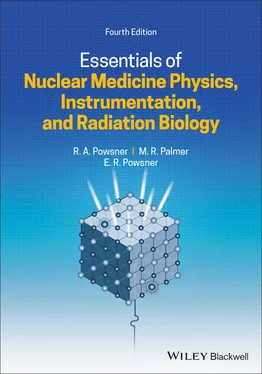

Figure 2.3 Angle of photon scattering.